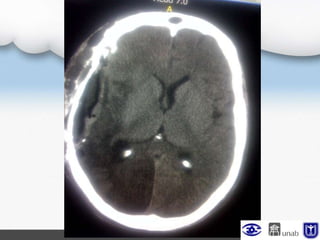

TAC cerebral